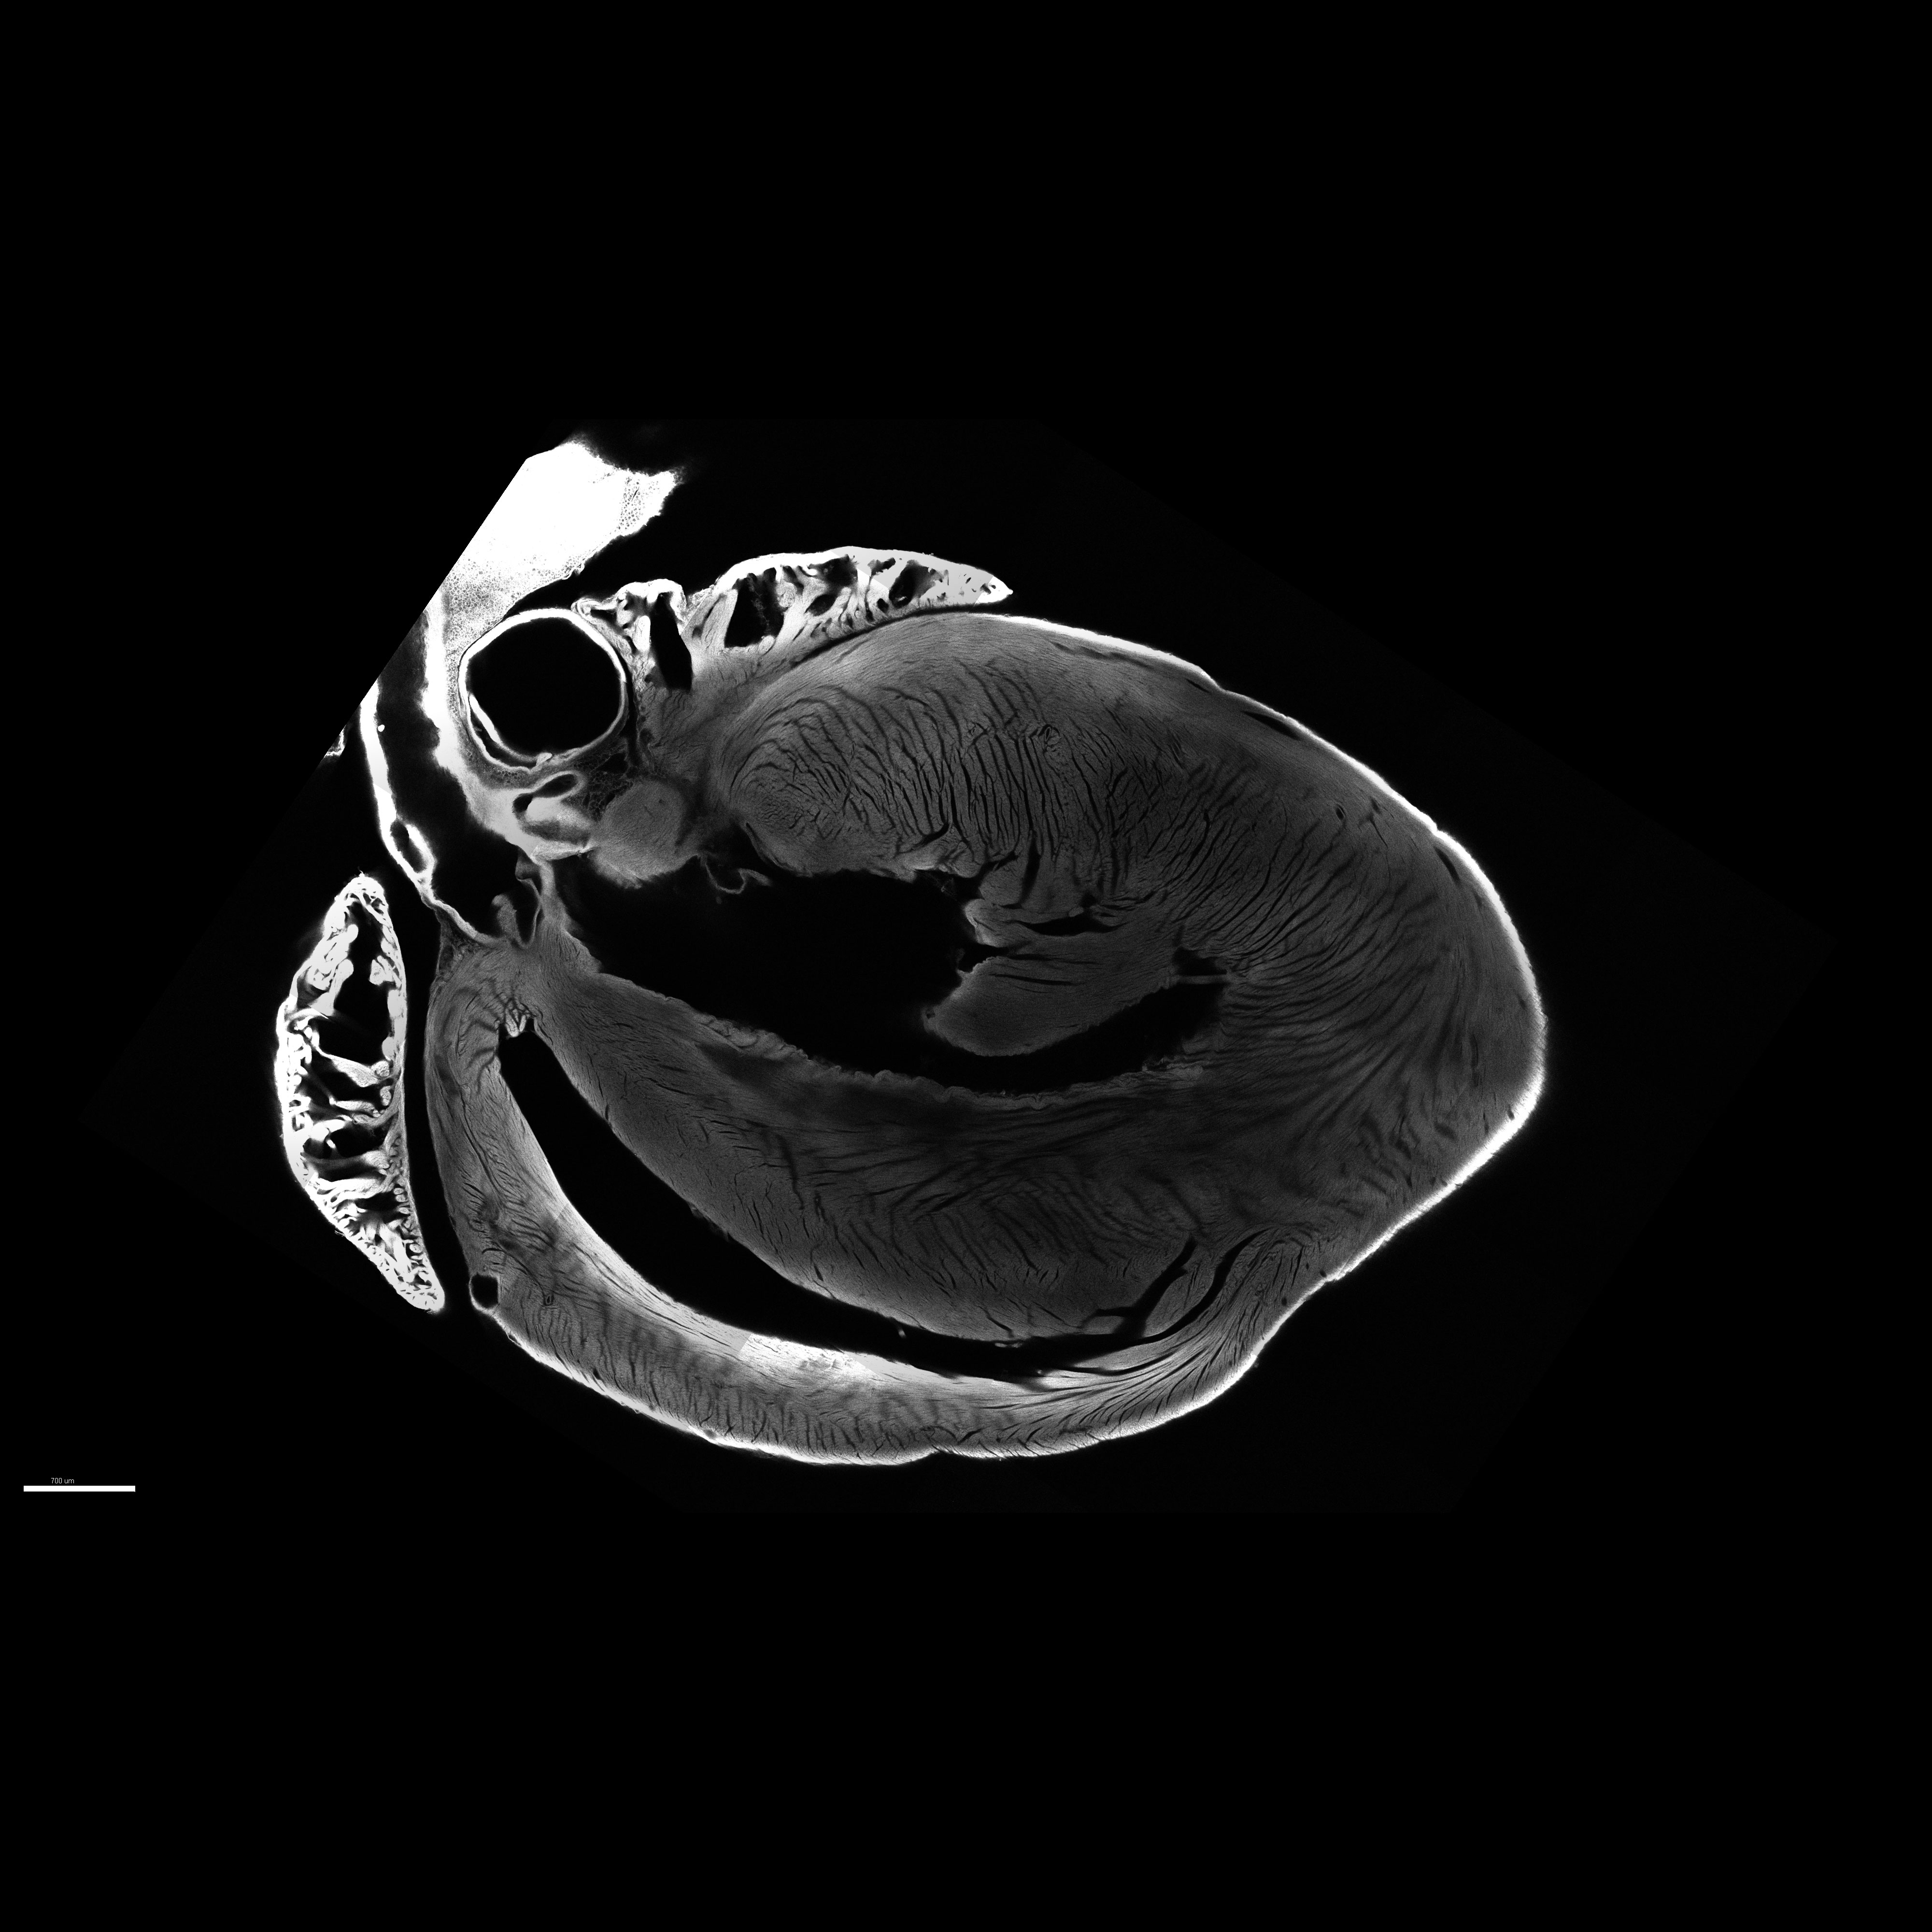

Image of a mouse heart cleared and imaged using the LSM 710 Two-photon microscope.